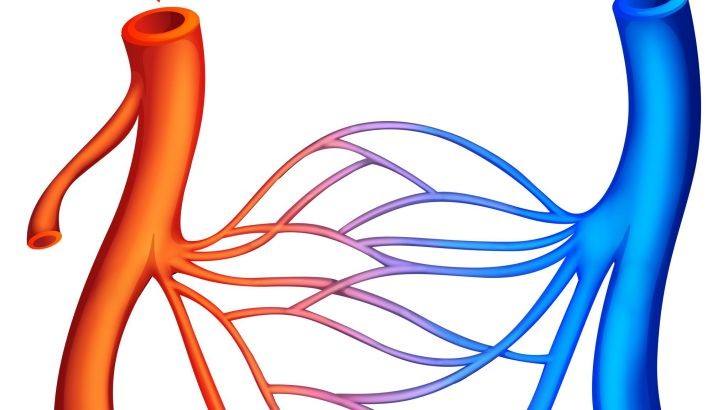

Oxygen and carbon dioxide are transferred in the body through blood arteries called _.

distributing arteries

arterioles

capillaries

venules

Plaque buildup in the artery walls is known as _ .

arteriosus

atherosclerosis

arterioclogus

arterionecrosis

What is an aneurysm?

A ballooning of a region of an artery

Inflammation of the capillaries

Inflammation of the brain

Inflammation of the arteries